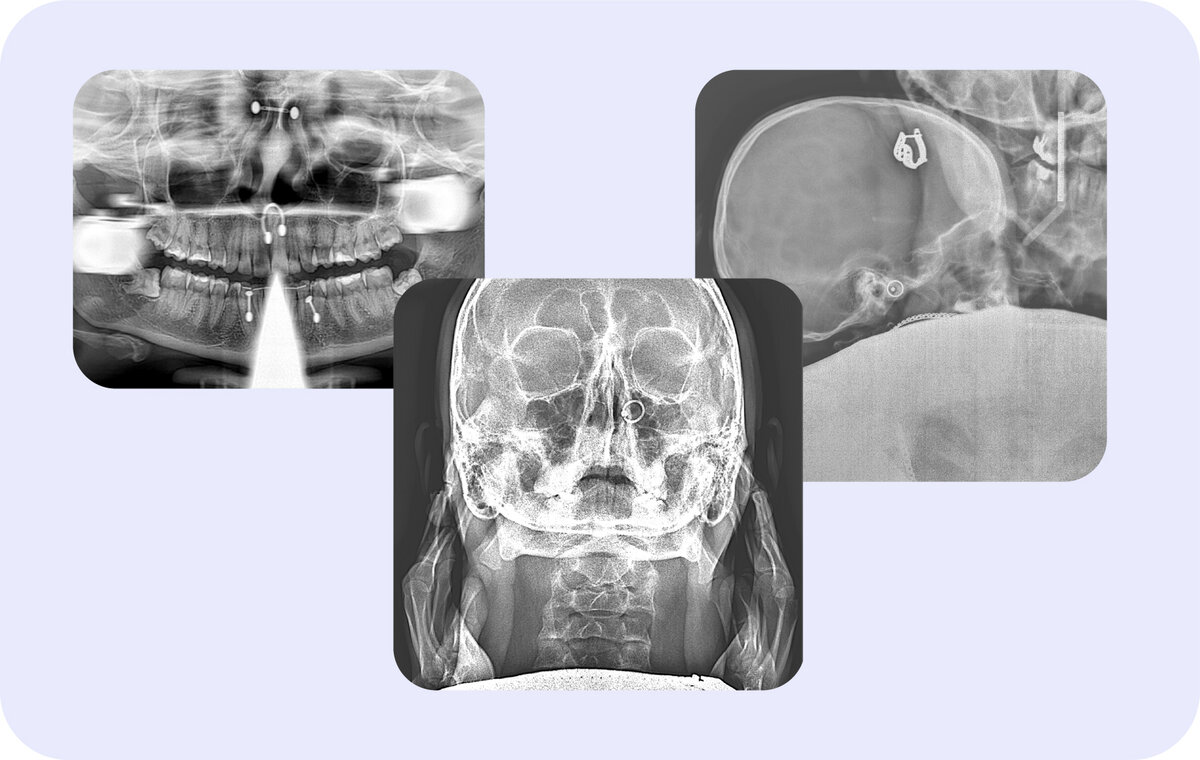

«Серёжки оставить можно?»: почему перед рентген-исследованием нужно снимать металлические украшения

Метод получения снимка челюстно-лицевой области заключается в сканировании головы при помощи рентгеновских лучей. Они проходят сквозь исследуемый участок и фиксируются на детекторе. На пути лучей могут возникать помехи — металлические предметы, которые влияют на качество снимка.

Металл, если не снять его перед диагностикой, визуализируется яркими пятнами. Это связано с высокой плотностью вещества: рентген-лучи не могут пройти, например, сквозь золотые серьги или пирсинг.

Засветы на снимке специалисты называют «артефактами». Они помешают просмотру ближайших структур: зубов, костей черепа, суставов, пазух. За засветами могут скрываться патологии, которые врач не увидит.

Несъёмные металлические конструкции не являются противопоказанием для рентгенодиагностики. Например, в случае с несъемными коронками и протезами в центрах «Пикассо» пациент может сделать снимок на томографе с функцией подавления артефактов от металлов.